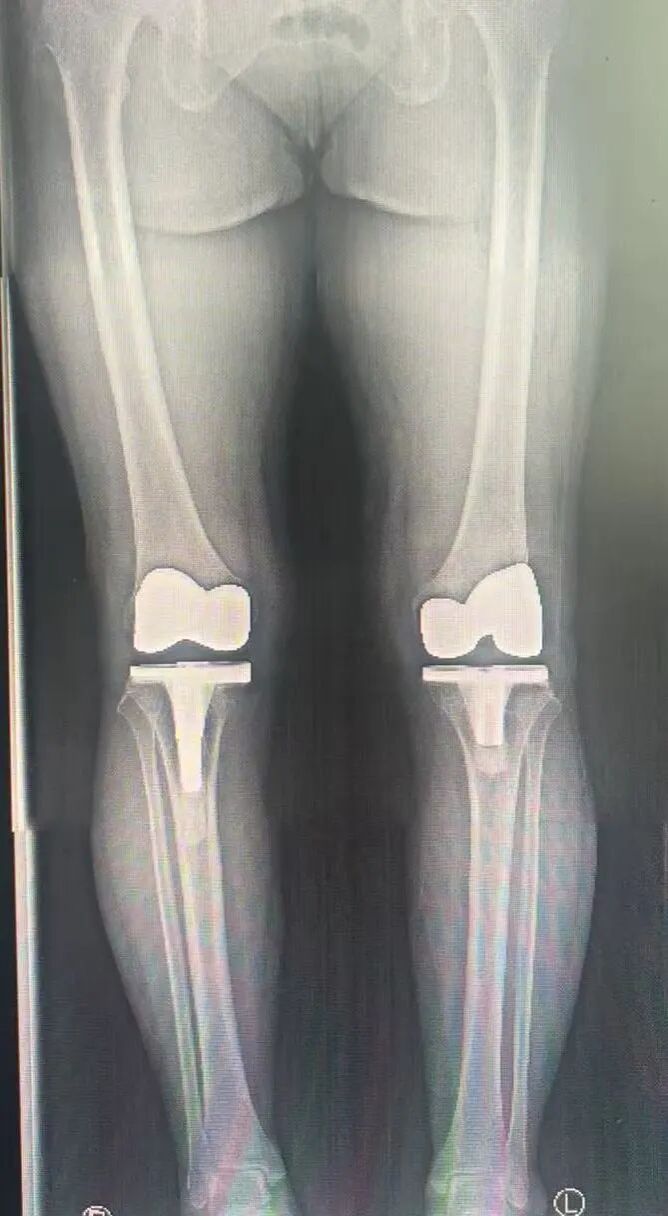

近日,为了彻底摆脱关节炎困扰,她再次来到医院,希望将左膝也进行置换。王国华团队经过周密讨论,再次为她成功实施左膝人工关节置换术。

术前VS术后对比

术后第二天,在医生指导下积极康复的苗阿姨,已经能自行下地行走,她拉着医护人员的手笑着说:“我觉得这次恢复得比上次还快!一想到以后两条腿都不疼了,还能去公园遛遛弯,我做梦都能笑醒,真后悔当初没早点来治!”